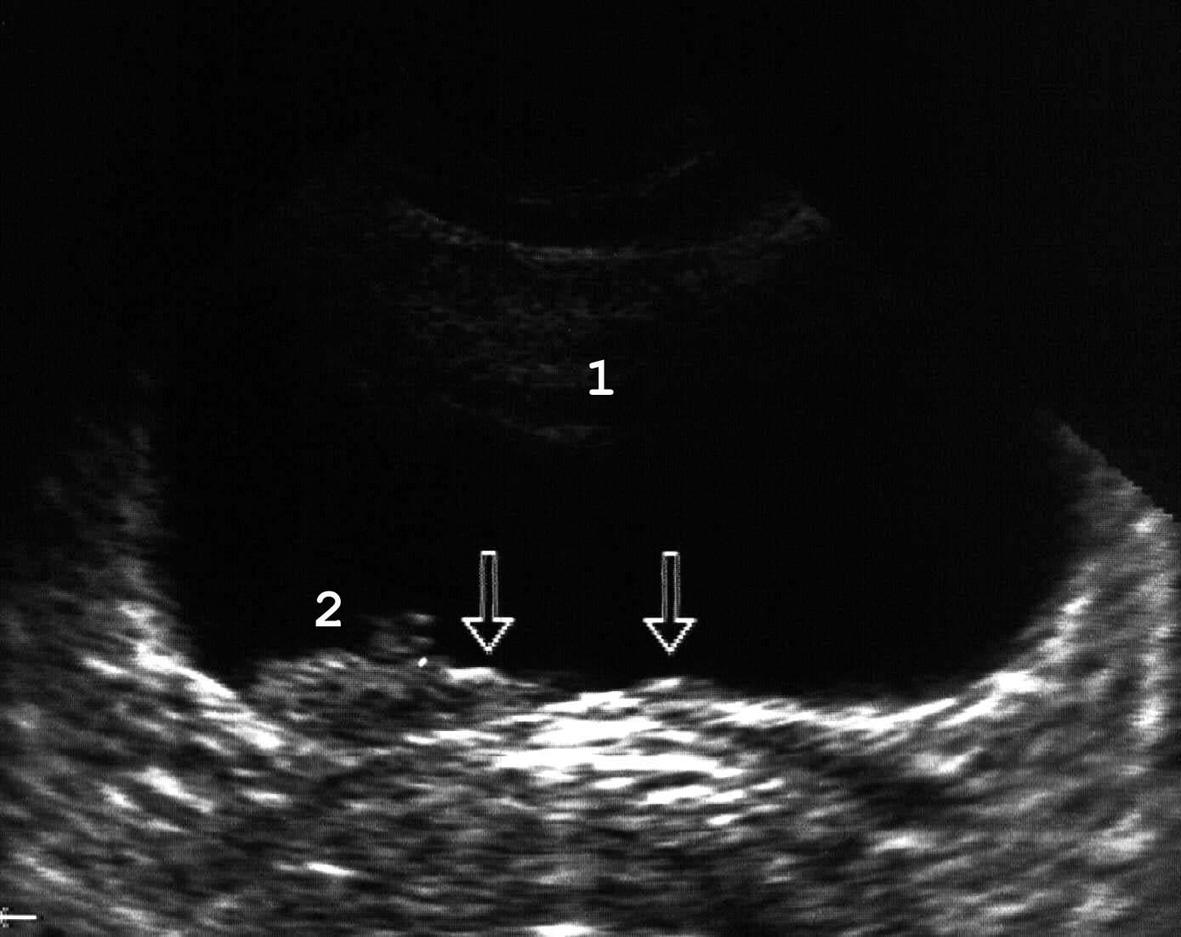

Рис. 14. Сонограммы мочевого пузыря с уретероцеле: 1 − мочевой пузырь; 2 − уретероцеле; 3 − горизонтальный уровень эхогенного осадка при пиурии. (Поперечное сканирование, секторный датчик 5 МГц, “Siemens SL-1”).